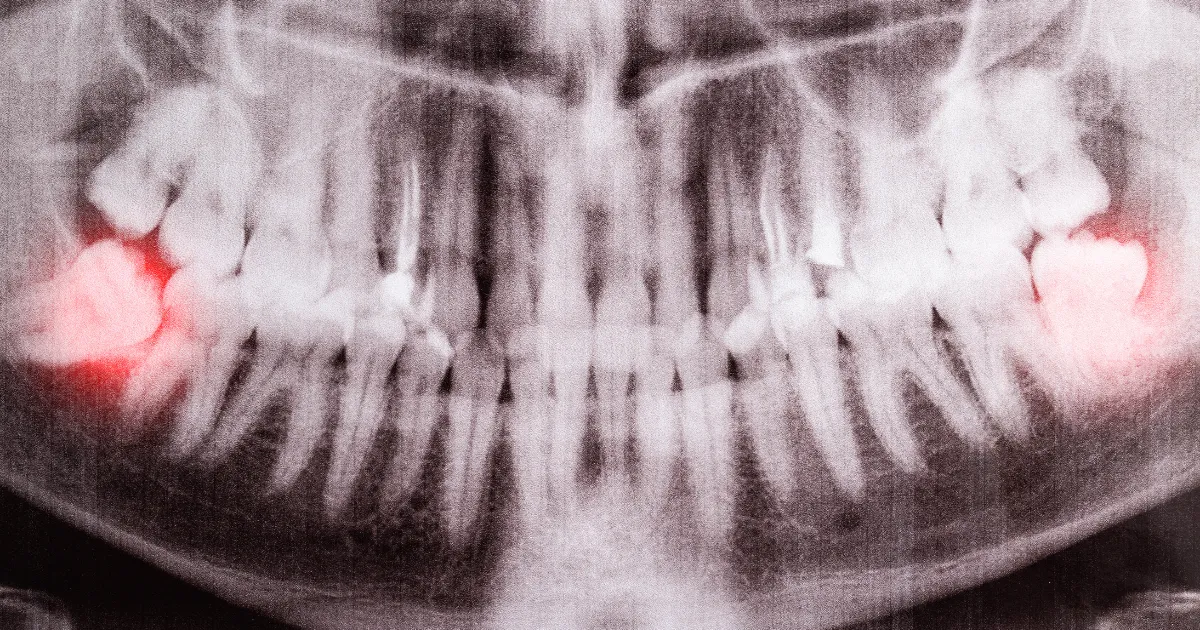

親知らずが部分的に生えた状態(半埋伏歯)は、歯茎と歯の間に食べかすや細菌が入り込みやすく、智歯周囲炎を引き起こします。

- 斜めや横向きに生えている

歯科ハミール高田88では、CT撮影や最新の3Dスキャナー「iTero」を導入しており、抜歯前の詳細な診断を行います。

これにより、歯の位置や形状、周囲の骨構造を正確に把握し、リスクを最小限に抑えた安全で確実な治療が可能です。

CTによる立体画像解析により、神経や血管の位置も明確にし、難易度の高い親知らずの抜歯にも対応しています。